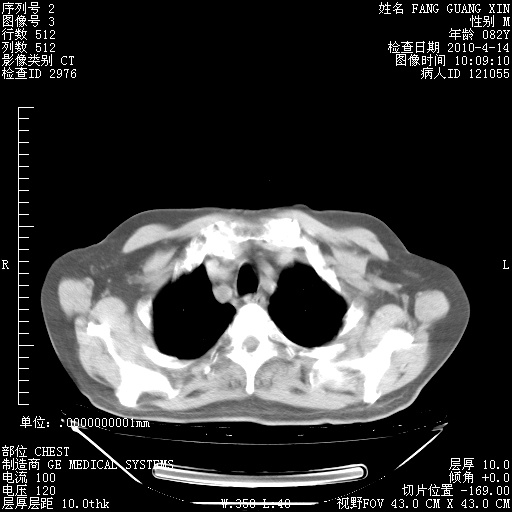

4月14日肺部CT

楼主| 发表于 2010-4-28 16:51 | 显示全部楼层

楼主| 发表于 2010-4-28 16:53 | 显示全部楼层

肺部CT平扫未见异常。